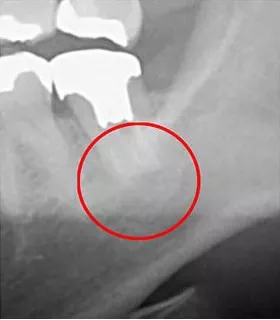

2次元と3次元の撮影では、可視化できる範囲に大きな違いがあります。下の画像をご覧ください。丸がついている部分が問題のある箇所です。同じ部位を撮影した2次元レントゲン(左)と3次元CT(右)の比較では、3次元の方が問題箇所を明確に捉えることができますが、2次元ではその詳細が見逃されがちです。

このように、2次元レントゲンのみでの診断では、見落としが生じるリスクがあり、これは歯科医療において大きな問題となります。当院では、患者様の状態を「しっかりと見える化」するため、3次元CTを用いた詳細な診査診断を行っています。